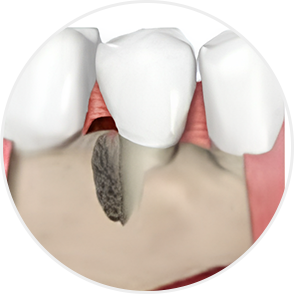

What is Periodontal Disease?

Periodontitis — commonly known as gum disease — is one of the most prevalent conditions

that destroys the gingiva and alveolar bone.

It begins with simple gum swelling

and bleeding,

but if left untreated, the alveolar bone gradually resorbs,

ultimately leading to tooth extraction.

Moderate–Chronic Periodontitis

Tooth mobility increases; gingival recession exposes tooth roots

Even when severe periodontal disease has caused gingival recession and alveolar bone resorption, teeth can often be preserved through gum regeneration therapy using Emdogain. This procedure regenerates damaged alveolar bone and surrounding periodontal tissue. By applying Emdogain — a specialized gel that stimulates periodontal tissue regeneration — the supporting structures of the tooth are rebuilt, allowing function and health to be restored without extraction.